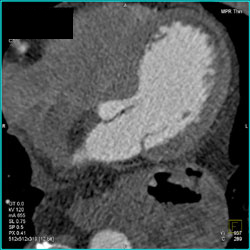

Patent Stent in LAD